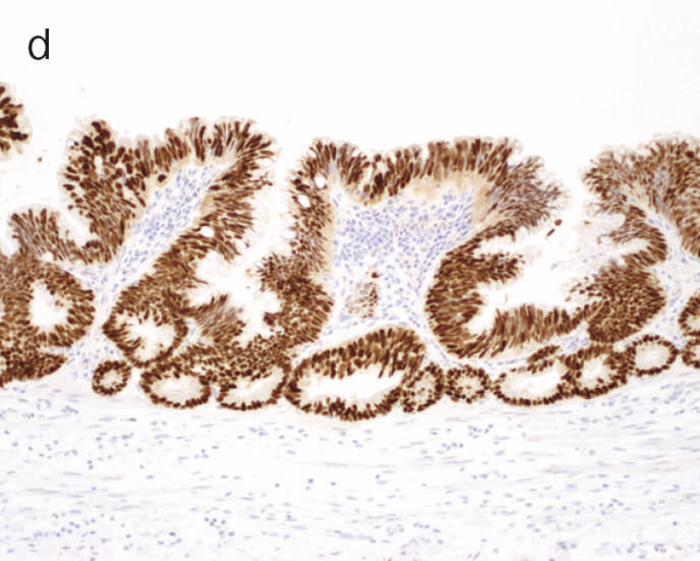

図9 Dysplasiaの代表的な組織像

- LGDの組織像(HE染色):異型腺管では表層への分化傾向が見られる。

- aのp53免疫染色:異型腺管深部側優位にp53蛋白過剰発現が見られる。

- HGDの組織像(HE染色):異型腺管では表層まで核腫大と重積が認められる。

- cのp53免疫染色:異型腺管表層部までp53蛋白の過剰発現が見られる。

表層への分化傾向を示すLGDでは異型腺管深部側優位にp53蛋白過剰発現が見られるのに対し,散発性腺腫ではp53蛋白異常発現は認められない。また,Ki-67(増殖マーカー)染色においては,LGDでは細胞増殖帯が粘膜深層~中層に位置するが(bottom-up pattern),散発性腺腫では細胞増殖帯が腺管表層~中層に分布する(top-down pattern)(CQ 12,CQ 13)。